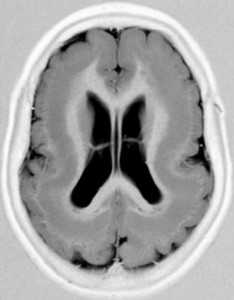

МРТ. Т1-зависимая аксиальная томограмма. “Двойная кора”.

Если нейроны совсем не достигают коры, то возникает лиссэнцефалия. Если только часть нейронов не достигает её, то возникают субкортикальные гетеротопии, видимые при МРТ в виде узлов или полосы («двойная» кора). Клиническая симптоматика обычно негрубая - небольшое отставание развития, пирамидные знаки и, иногда, дизартрия.